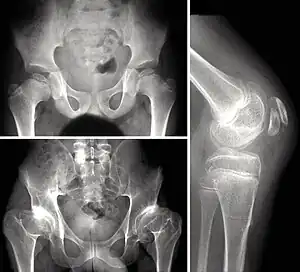

Children with autosomal dominant MED experience joint pain and fatigue after exercising. Their x-rays show small and irregular ossifications centers, most apparent in the hips and knees. There are very small capital femoral epiphyses and hypoplastic, poorly formed acetabular roofs.[1] A waddling gait may develop. Knees have metaphyseal widening and irregularity while hands have brachydactyly (short fingers) and proximal metacarpal rounding. Flat feet are very common.[2] The spine is normal but may have a few irregularities, such as scoliosis.

Children with recessive MED experience joint pain, particularly of the hips and knees, and commonly have deformities of the hands, feet, knees, or vertebral column (like scoliosis). Approximately 50% of affected children have abnormal findings at birth (such as club foot or twisted metatarsals, cleft palate, inward curving fingers due to underdeveloped bones and brachydactyly, or ear swelling caused by injury during birth). Height is in the normal range before puberty. As adults, people with recessive MED are only slightly more diminished in stature, but within the normal range. Lateral knee radiography can show multi-layered patellae.[3]

Symptomatic individuals should be seen by an orthopedist to assess the possibility of treatment (physiotherapy for muscular strengthening, cautious use of analgesic medications such as nonsteroidal anti-inflammatory drugs). Although there is no cure, surgery is sometimes used to relieve symptoms.[18] Surgery may be necessary to treat misalignment of the hip (osteotomy of the pelvis or the collum femoris) and, in some cases, malformation (e.g., genu varum or genu valgum).[19] In some cases, total hip replacement may be necessary. However, surgery is not always necessary or appropriate.[20]